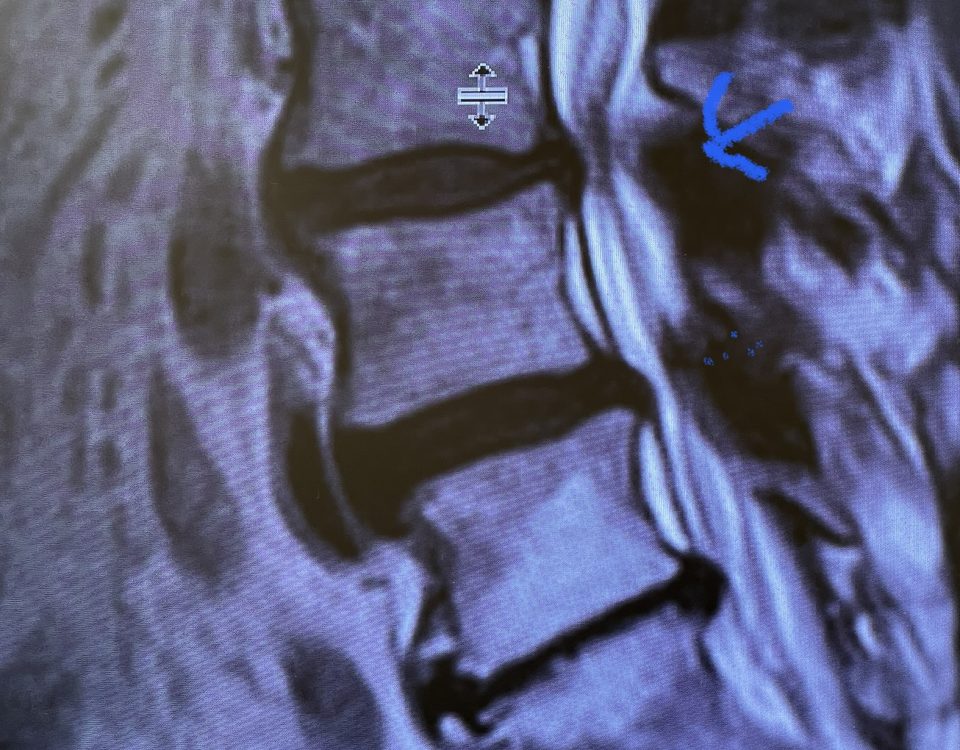

People are obsessed with cysts! When you think about it, the body likes to form cysts. Why does this happen? Cysts can form just about anywhere […]